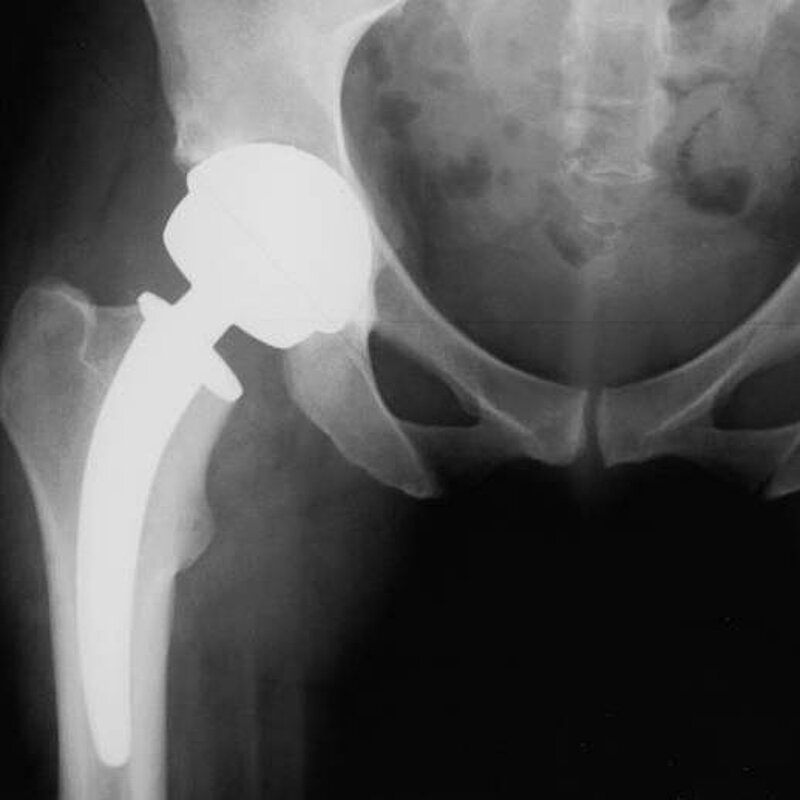

Prävention durch Stärkung konservativer Therapien, um Hüftoperationen eventuell zu einem späteren Zeitpunkt durchzuführen, wird aktuell gefordert.

BVOU und DGOU sehen im Endoprothesenregister, an dem Krankenkassen und Patienten beteiligt

sind, einen wichtigen Schritt zu Qualität und Patientensicherheit.